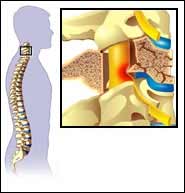

آسیب شبکه بازویی (براکیال) یا آمیوتروفی نورالژیک، وضعیتی است که در آن عصبهای واقع در اندامهای فوقانی بدن خصوص دستها، بازو و شانهها ملتهب میشود. عصبهای واقع در شانهها، بازوها دستها شبکهای را بنام شبکهی براکیال (شبکهی عصبی) تشکیل میدهند که از طناب نخاعی شروع و تا شانه و بازو کشیده میشود. التهاب شبکهی عصبی (نوریت) میتواند منجر به آزردگی و دردی بی امان در شانهها شود و وقتی درد برطرف شود، شانهها و بازوها دچار ضعف شدیدی میشوند و حرکت دادن آن برای شما دشوار خواهد بود.

- عصبهای شبکهی بازویی از ورودیهایی در ستون فقرات گردنی میگذرند. این عصبها میتوانند با وارد شدن صدماتی مانند سقوط از بلندی، جراحات یا آسیبهای ورزشی آسیب ببینند. آسیب ورزشی معمول دیگری به نام “سندروم برنر” یا ” سندروم استینگر” اکثر اوقات در فوتبالیستها رخ میدهد که شانهها بهسختی با بازیکنان دیگر برخورد میکند. ضربهی مستقیم شانه را به پایین و گردن را به ست مخالف میکشاند، درنتیجه باعث کشیده و فشرده شدن عصبها میشود.